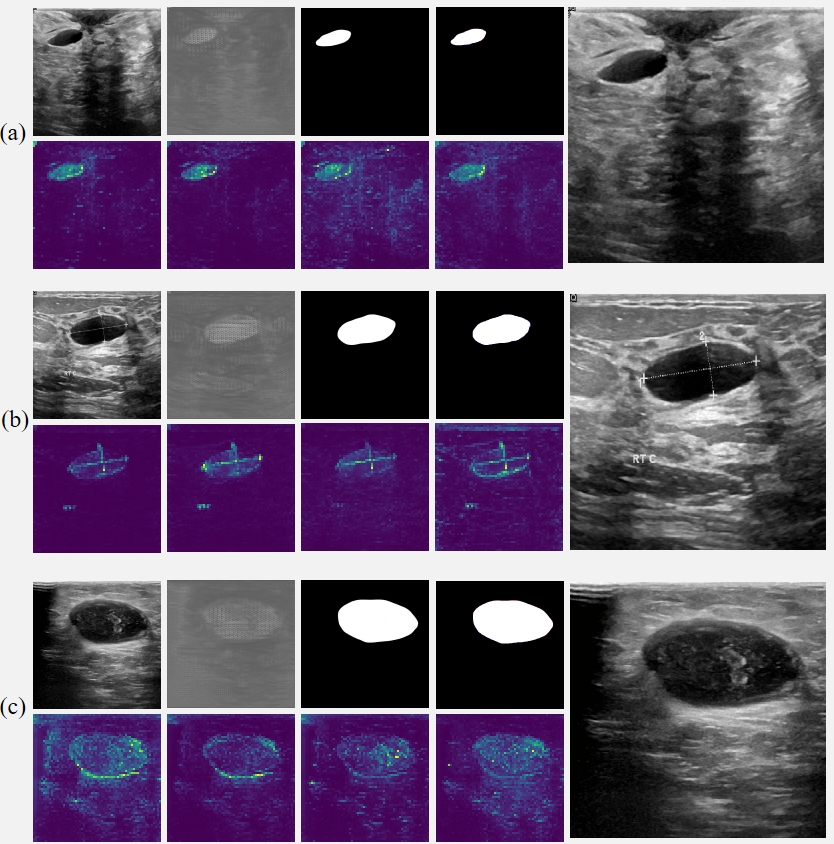

Fig. 5 Intermediate results of RAMIS on breast tumor ultrasound image segmentation dataset. (a-c) The first row in each group of pictures from left to right is the input image, initial segmentation image, final segmentation image, prediction and Ground Truth comparison results (red indicates false negatives, blue indicates false positives). All the pictures in the second row are the output results of the self-distillation module. The last picture in each group shows the results after magnifying the implicit neural expression by twice the resolution.